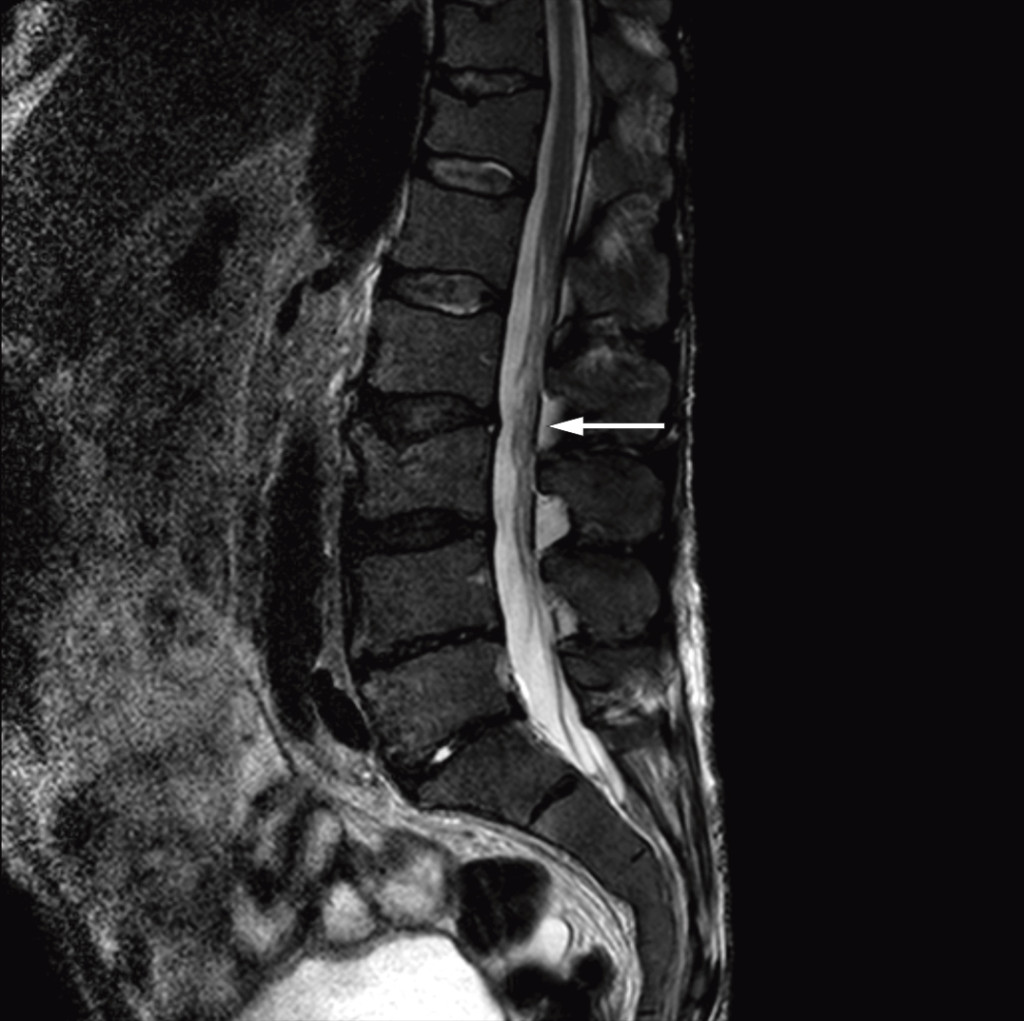

After the diagnosis Bing-Neel syndrome had been made, we studied the MRI images of the cerebrum and lumbosacral column again and found pathologically thickened and contrast-enhanced meninges over both cerebral hemispheres (Fig. 1) and the cerebellum, and wavy, thickened cauda equina roots (Fig. 2). We concluded that the thickened meninges were an expression of diffuse affection of the central nervous system, consistent with Bing-Neel syndrome. The finding of thickened cauda equina roots was also assumed to be related to the syndrome, but this could not be determined with certainty since the changes were limited, and the images had unfortunately been taken without contrast.

Figure 2 Sagittal T2-weighted MRI image of the lumbosacral column shows wavy, thickened cauda equina roots.